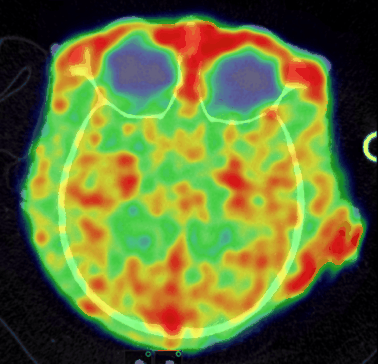

CASE 1: NHP PET/CT FDG brain imaging

• Courtesy of: University of Tours, Preclinical imaging department - PST ASB

Research objective: Investigation of FDG uptake in NHP brainĀ

Animal model: Female Macaca fascicularis, 4.5 kg

Acquisition protocol: PET imaging: 15 min per bed, 2 bed positions, 40 min after injection. CT imaging: 80kV, 52s per bed, 2 bed positions.

Processing and reconstruction protocol: PET: 3D OSEM, 0.84 mm isotropic voxel size. CT: 0.16 mm isotropic voxel size.

Biomarker or contrast agent: 18F-FDG; Injected activity: 85 MBq i.v.